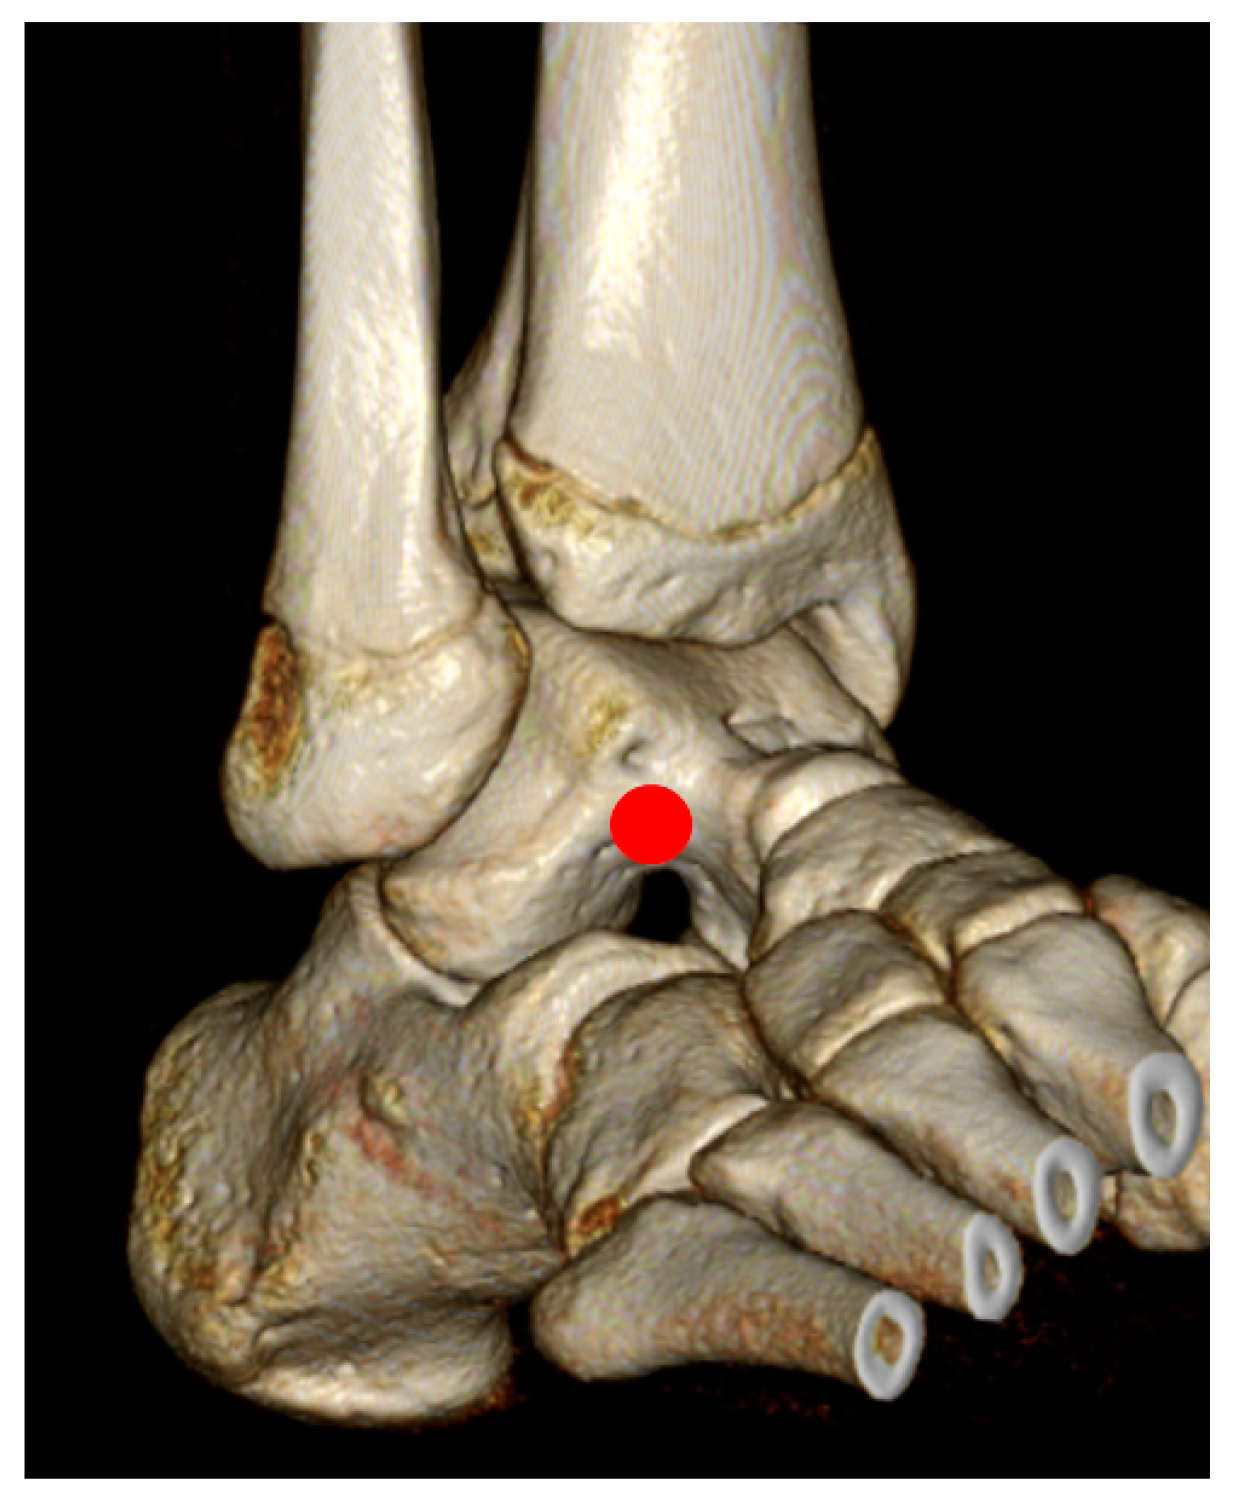

2.2. Surgical Techniques